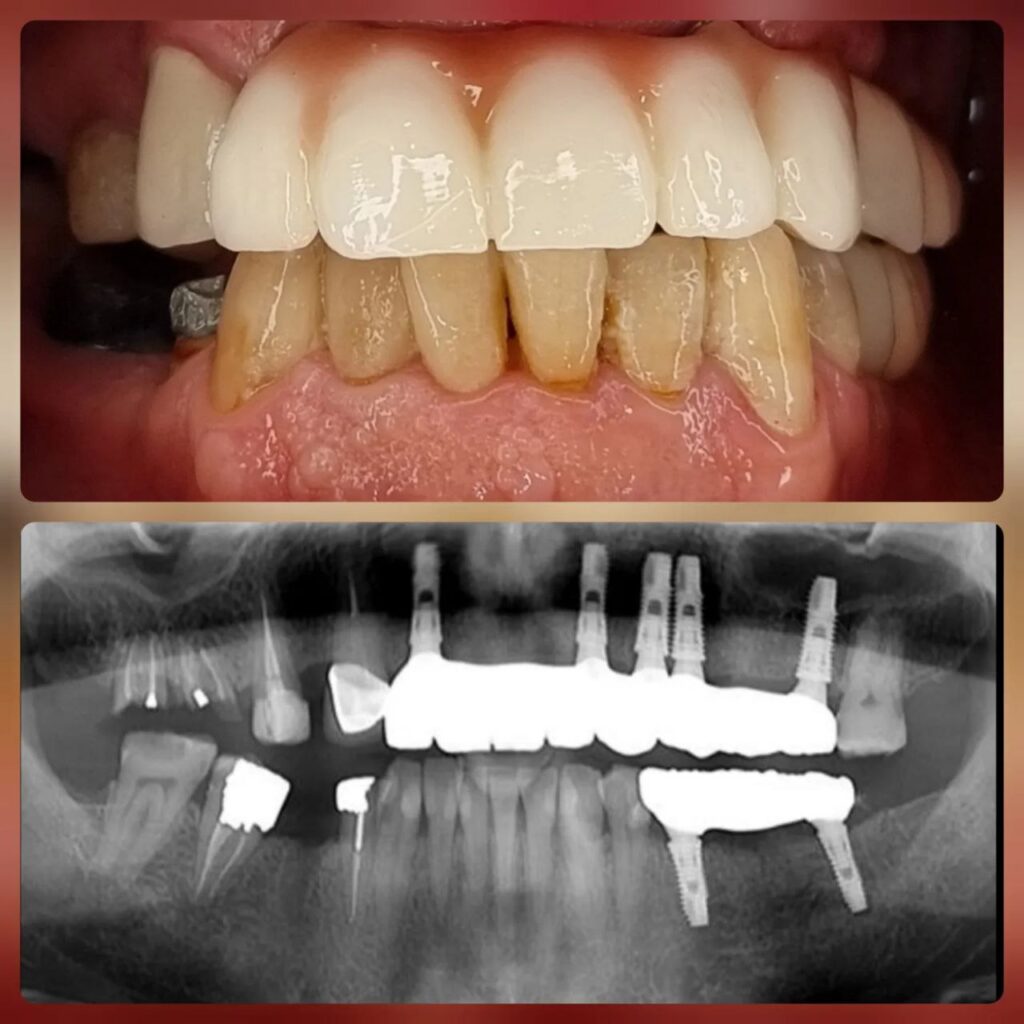

کاشت ایمپلنت دندان

اطمینان حاصل کردن از اینکه دندانهایتان به نحوی زیبا و طبیعی جایگزین شدهاند، از اهمیت بسیاری برخوردار است. ایمپلنت دندان به عنوان یک روش درمانی دائمی در دندانپزشکی شناخته میشود که حاصل آن، یک دندان زیبا و طبیعی در دهان شما خواهد بود.

هرچند که این روش درمانی هزینهی بیشتری نسبت به روشهای دیگر دارد، اما ارزش زیبایی که ایجاد میکند، قابل انکار نیست. ایمپلنتها به قدری شبیه به دندانهای طبیعی هستند که به سختی میتوان آنها را از دیگر دندانها تشخیص داد.